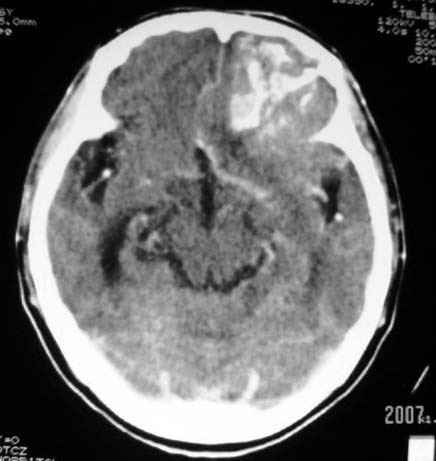

标题: CT7268:左额顶部病变增强片. [打印本页]

标题: CT7268:左额顶部病变增强片.

比较典型的少枝胶质细胞瘤ct表现,局部额骨垂直板有侵蚀变薄。

左额叶病灶内条片状高密度是钙化吗?是的话考虑少支胶质瘤可能大。不然有脑血畸形伴出血可能。

左侧额顶叶有条带状钙化的不规则形占位,增强呈不均匀轻度强化,局部颅骨受侵蚀变薄,典型的少支胶质细胞瘤。

比较典型的少枝胶质细胞瘤ct表现,局部额骨垂直板有侵蚀变薄